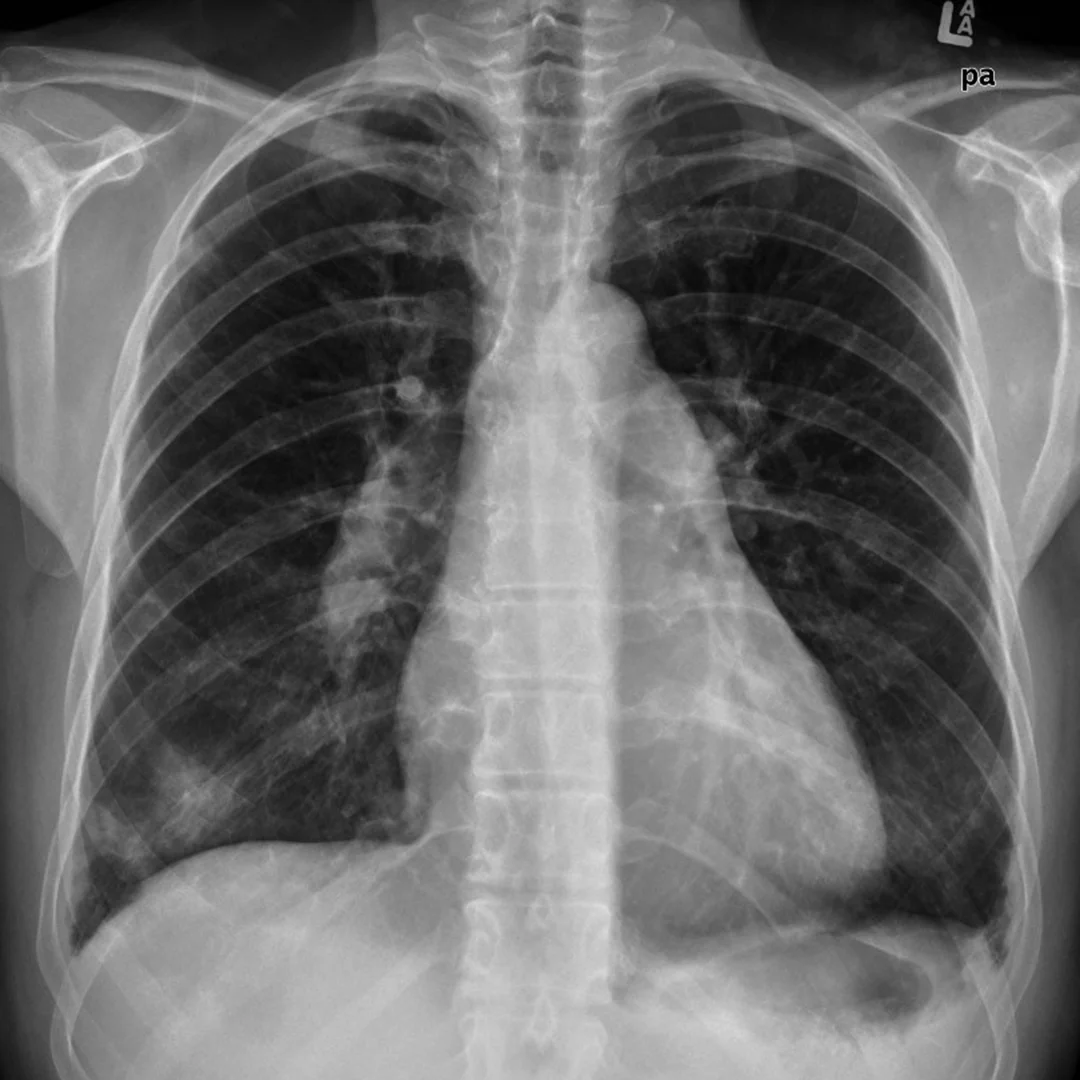

What chest x-ray findings may be seen in pulmonary arterial hypertension?

{{c1::Elevated cardiac apex due to right ventricular hypertrophy

Enlarged right atrium

Prominent pulmonary outflow tract

Enlarged pulmonary arteries

Pruning of peripheral pulmonary vessels

Radiographic correlates of underlying causes*}}

An enlarged cardiac silhouette with prominent pulmonary trunk and pulmonary arteries proximally.

Case courtesy of Frank Gaillard, Radiopaedia.org, rID: 8653